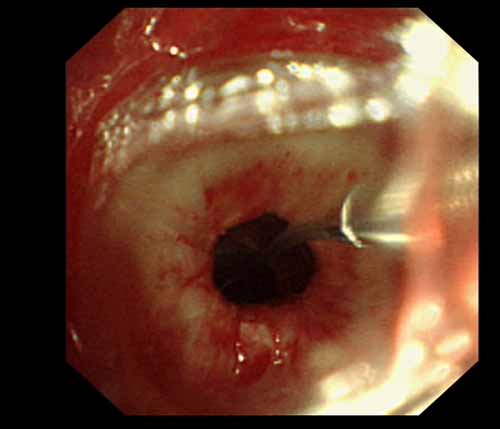

患者李某某,女,45歲,因氣管插管咳嗽、喘憋10天入院。頸部CT檢查示聲門下約20mm處氣管明顯狹窄,狹窄段長約26mm,最窄處直徑約4.4mm。支氣管鏡檢查見聲門下約2cm氣管呈漏斗狀縮窄,直徑約4-5mm,支氣管鏡無法通過。經(jīng)科室討論,決定行電子支氣管鏡下氣管球囊擴張治療。與患者及家屬充分溝通并經(jīng)三方見證談話簽署知情同意書后,在患者持續(xù)吸氧、局麻下,科主任于世倫主任醫(yī)師帶領(lǐng)治療小組為患者實行電子支氣管鏡下氣管球囊擴張術(shù)。手術(shù)過程順利,出血量很少,術(shù)后患者呼吸困難癥狀即可明顯緩解。10天后行二次擴張,患者日?;顒訜o明顯喘憋,二次術(shù)后5天出院。

術(shù)后擴張開的氣管管腔